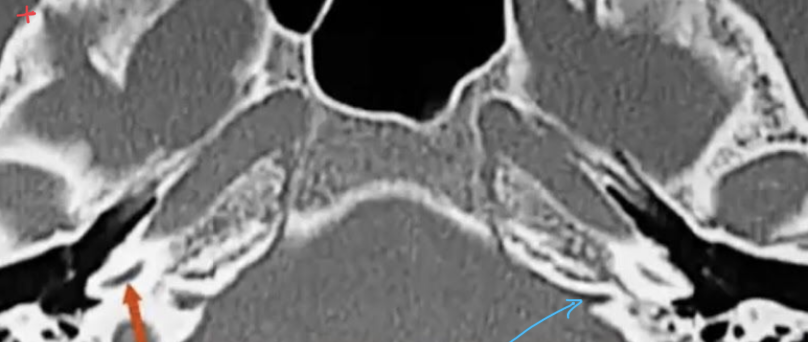

Tell the traject of the facial nerve in the skull base?

Nerves inside the IAC with subdivisions?

?